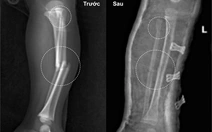

Các bác sĩ khuyến cáo cần chú ý đánh giá tình trạng nạn nhân trước khi đưa đi cấp cứu - Ảnh minh họa: BVCC